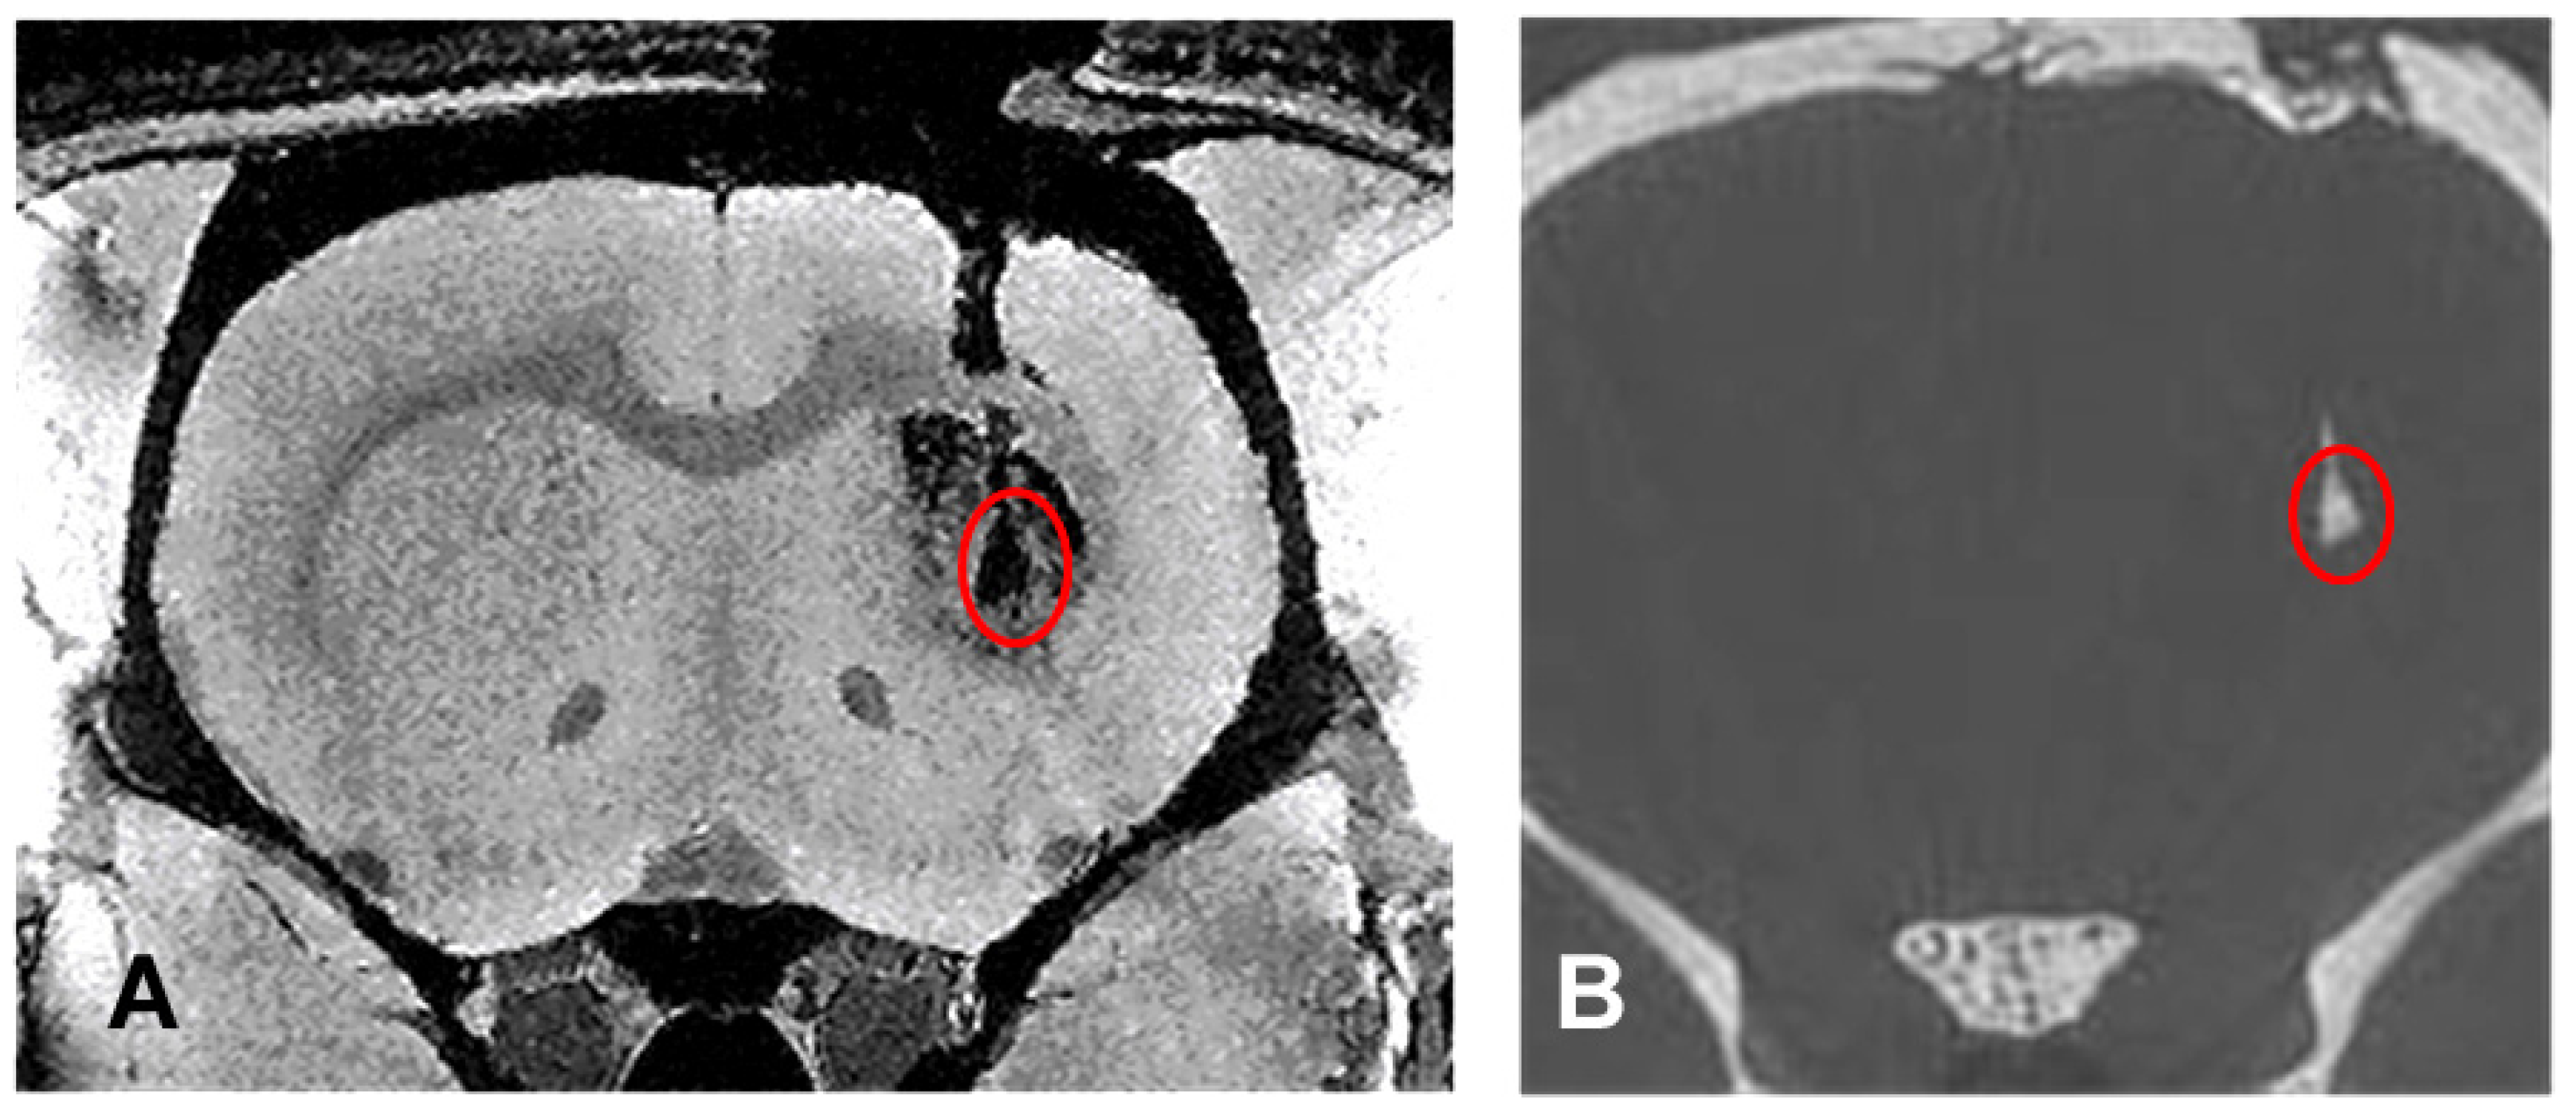

3.1. Comparison of Imaging Modalities